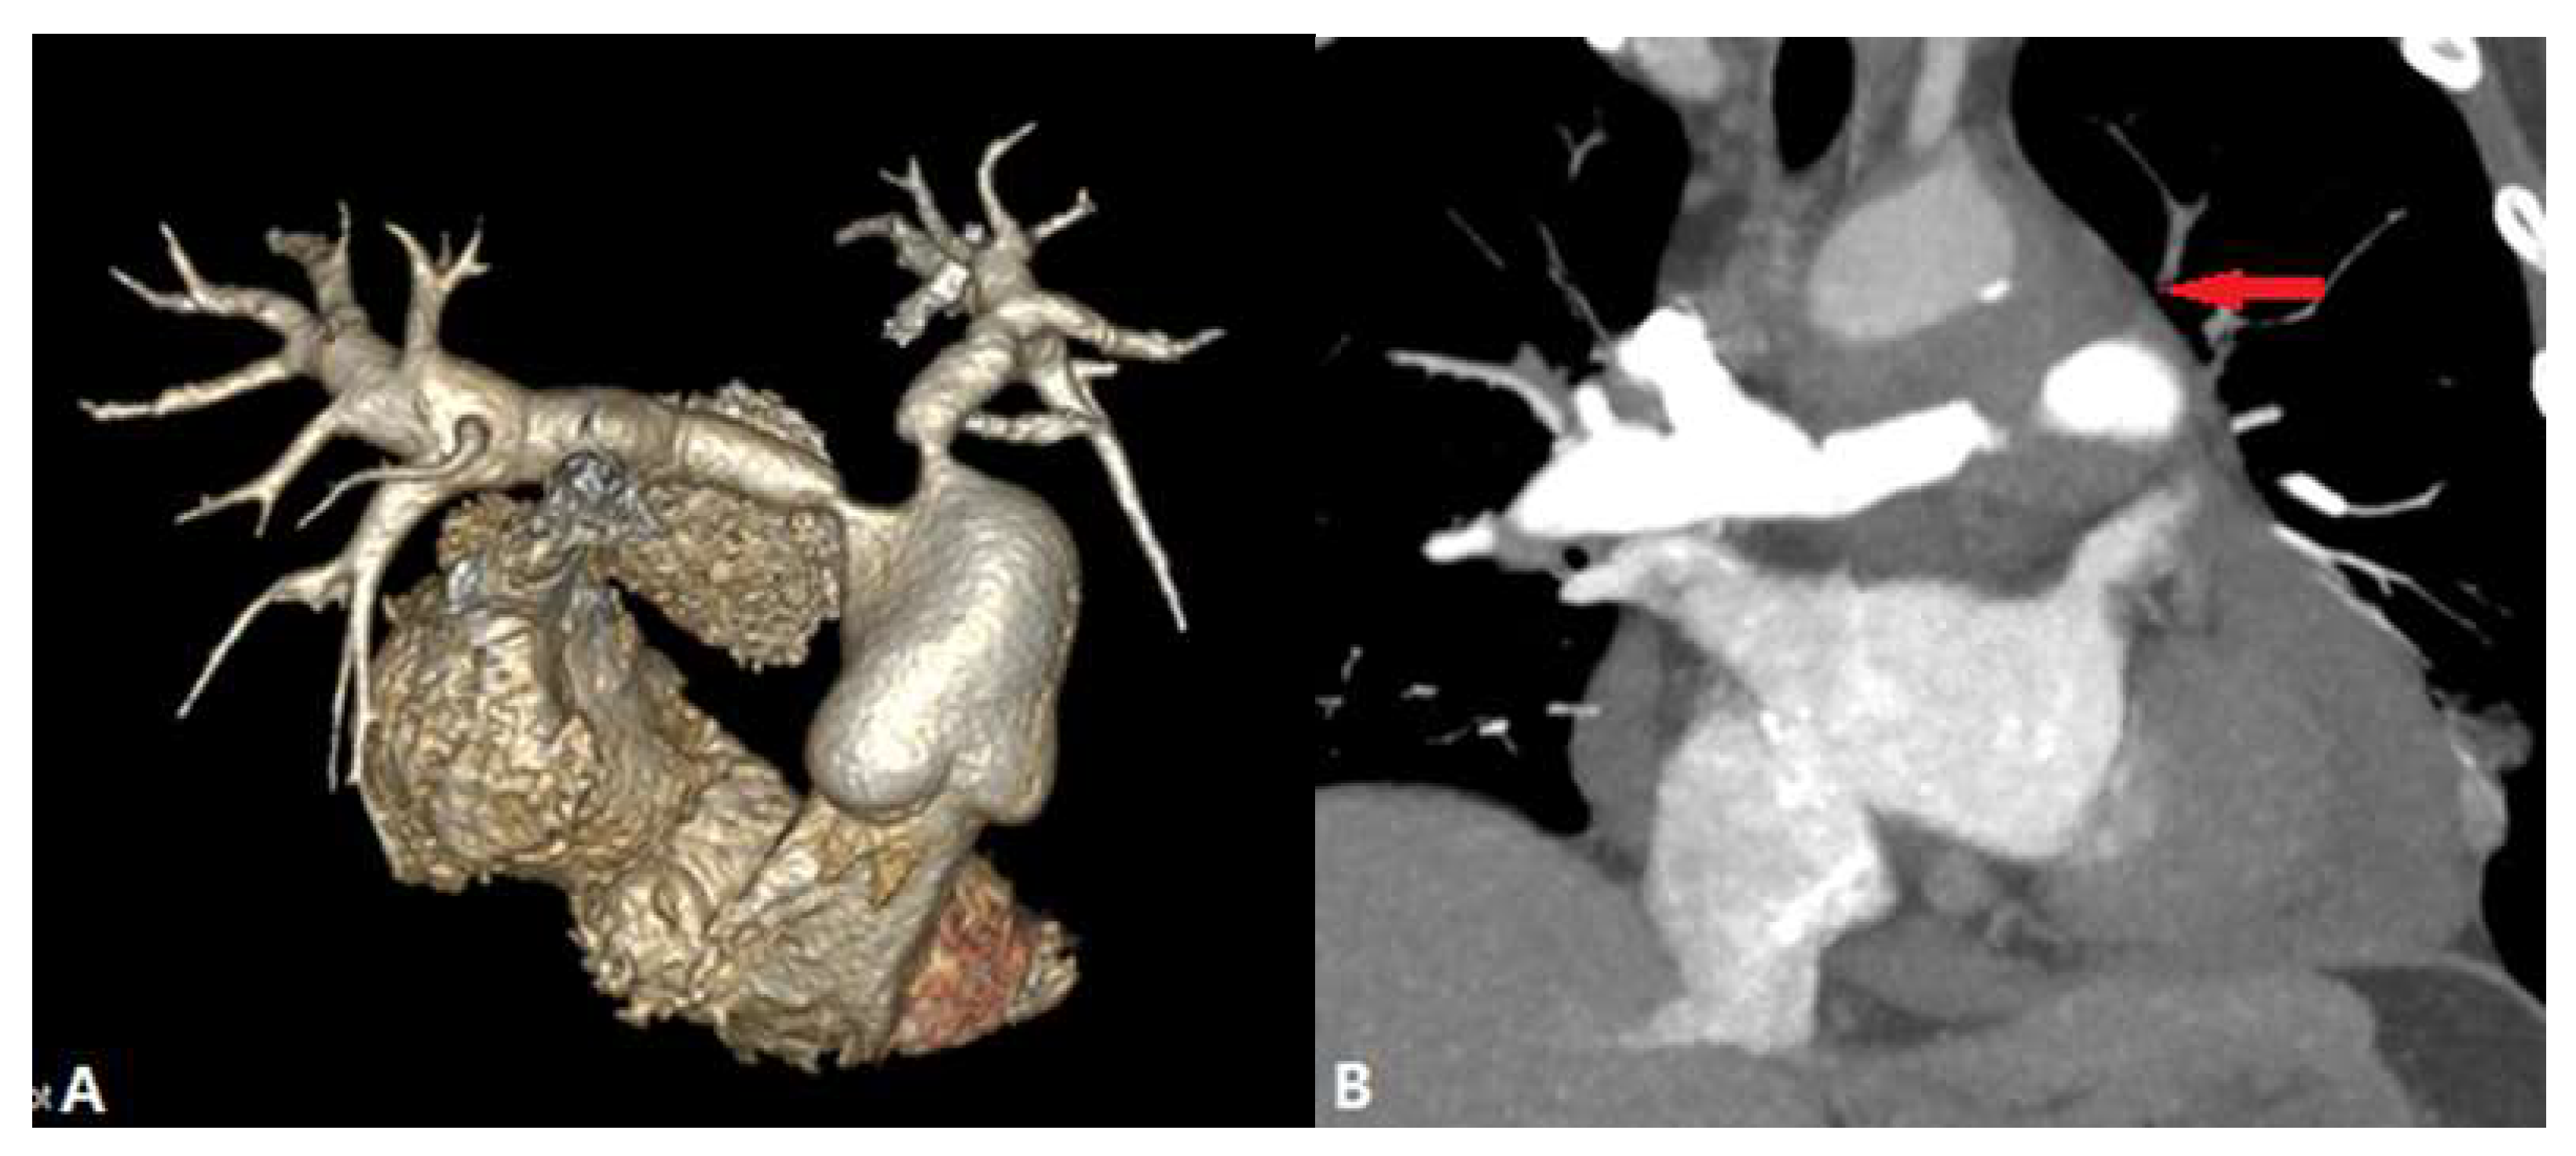

3.3.3. Aortic Aneurysm

4. Complications of Radiofrequency Ablation Of Atrial Fibrillation